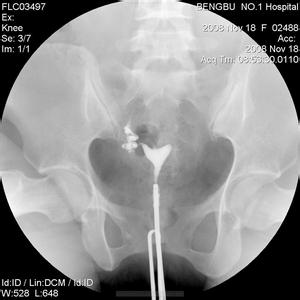

输卵管造影检查可清晰到病灶相关局部的形态,对所有软组织状态及活动情况均可明确判断,以诊断输卵管的堵塞部位以及内部功能。

相较输卵管通水即B超检查等方法,输卵管造影不仅可以有效防止检查引发的局部炎症迁延加重,还可将输卵管堵塞的诊断准确率大大提升,对后期明确治疗提供了有利支持和指导。

输卵管造影不仅是一种检查方法,还可对输卵管堵塞引发的某些不孕情况起到一定治疗效应,这是输卵管造影技术的一个明显优势。

输卵管造影是一种几乎无损伤、无任何后遗症和并发症等副作用的检查手段,在临床诊断输卵管堵塞的过程中,深受医生和患者的好评,是一种安全的诊断方法。

输卵管造影技术适用于诊断多种病症,如输卵管堵塞等各种女性局部病变,尤其可明确进行异物输卵管堵塞的诊断,以防造成误诊或漏诊等不良后果。